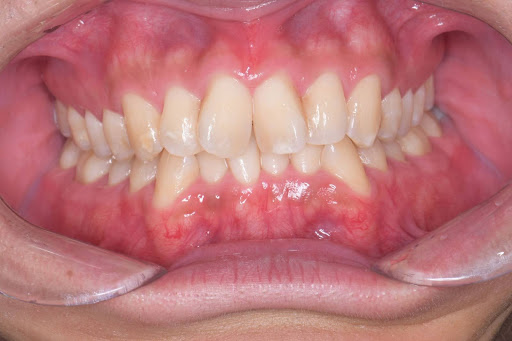

ガタつきのある歯並びも、マウスピース矯正でここまできれいに整えることが可能です。

<After>

【症例写真】豊富な経験に基づき、歯の重なりやアーチの形状を美しく改善します。

Before

After